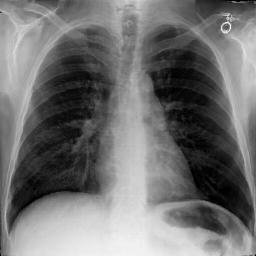

Fig. 3: Anonymization results. Real images XRX_{R} randomly selected from the training, validation, and test sets are displayed in the first column. The corresponding reconstructed images X^R\hat{X}_{R} are displayed in the second column. The anonymized images XAX_{A} are displayed in the last three columns.

Qualitative Results The visualization results are shown in Fig. 3. In this figure, the anonymized images optimized using only the utility loss ut\mathcal{L}_{ut} (column 3) exhibit greater visual similarity to their real counterparts (column 1), while those optimized using only the identity loss id\mathcal{L}_{id} (column 4) appear more distinct from their originals. Additionally, the anonymized images optimized with both the ut\mathcal{L}_{ut} and the id\mathcal{L}_{id} (column 5) strike a balance, appearing more realistic by simultaneously considering both identity removal and utility preservation.